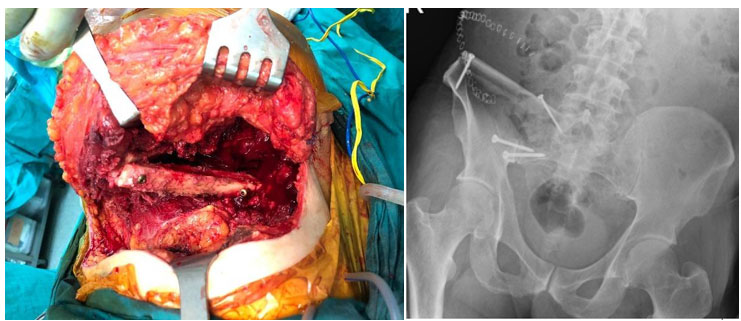

Ameliyat esnası ve sonrası: Kemiğin tümörlü kısmı çıktıktan sonra fibula kemiğinin araya yerleştirilmesi ve vidalar ile sabitlenmesi görülmekte